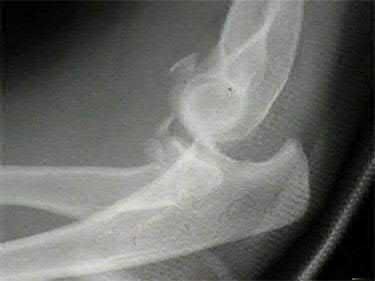

Question 12

A 55-year-old patient presents with a slowly enlarging, painful mass in the proximal humerus.

Biopsy reveals a hyaline cartilage matrix with cellular atypia, confirming a diagnosis of central conventional chondrosarcoma. Which of the following genetic mutations is most frequently identified in this specific tumor?

Explanation

Mutations in the isocitrate dehydrogenase genes, IDH1 and IDH2, are found in up to 50-60% of central conventional chondrosarcomas and enchondromas. EXT1 and EXT2 mutations are characteristic of multiple hereditary exostoses (osteochondromas). GNAS mutations are seen in fibrous dysplasia. TP53 and RB1 mutations are hallmark aberrations in osteosarcoma.